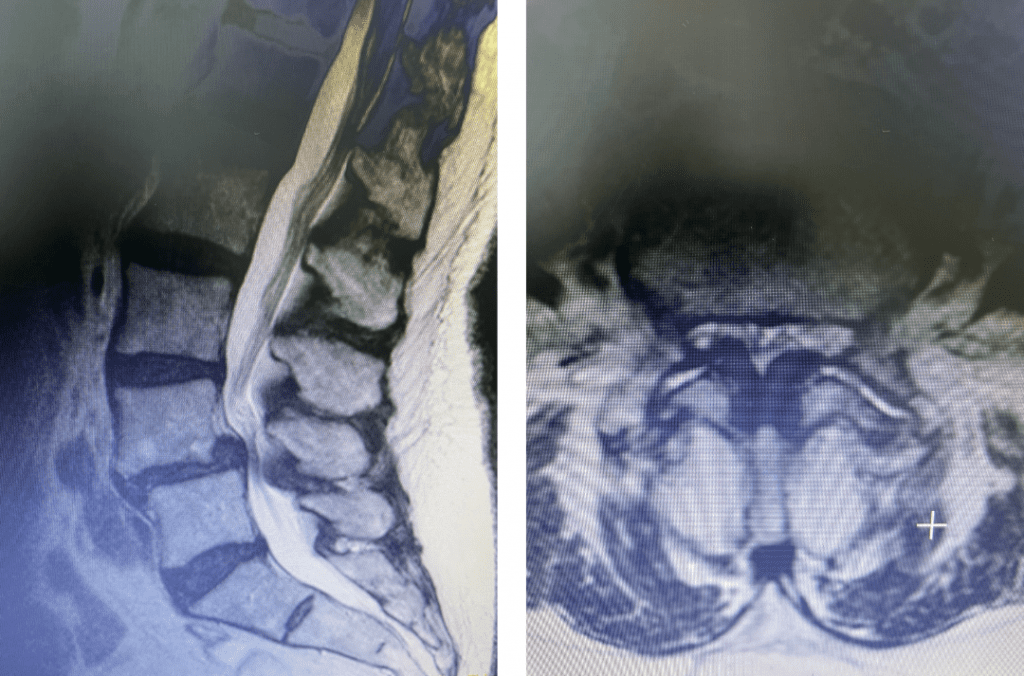

figure 1a and 1b lumbar stenosis

Figs 1a and 1b: T2 sagittal and axial lumbar MRI demonstrating severe L45 stenosis mainly secondary to thickened ligamentum flavum with a grade 1 spondylolisthesis at L45.

Lumbar stenosis is a fairly common condition I see in my office. Patients develop lumbar stenosis or narrowing of the spinal canal as a result of degenerative instability and laxity that is mainly age related. The body attempts to auto stabilize itself by forming stabilizing structures to compensate for instability such as thickening an already existing ligament or compensating by enlarging the facet joints which are the two regular joints on either side of the back of the spine in order to help improve stability. (Figs 1a and 1b) These structures are actually a form of arthritis and exert pressure on the canal in which the nerve sac travels through and the tunnel that the nerve leaves the spine. The spine does not know or care that the nerves are there and as a result the nerves get injured. The spine, at least the bony portion, is just taking care of itself. Patients are treated surgically for this by a procedure called a laminectomy which in essence restores the diameter of the spinal canal and the nerve tunnel by shaving away the arthritis. The trick of the laminectomy is to pick and dissect this sometimes soft and sometimes hard material from the nerve sac membrane for which it has been compressing for many years. Sometimes that material is really impaling the membrane which is called the dura. It is very important to do this gently in the manner in which we have been trained and avoid a tear or a leak in this membrane. This can happen and can be repaired with a stitch and some biological glue.